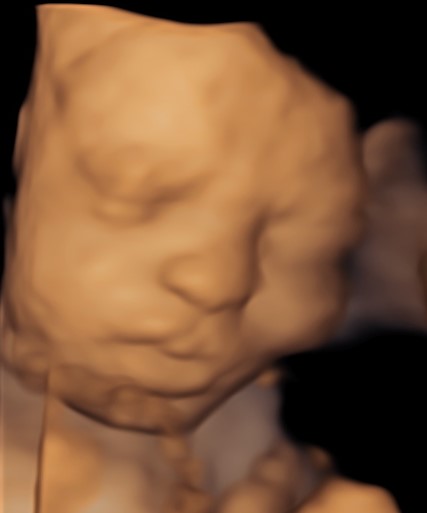

Monmouth County’s First 4D/5D/HD Live Ultrasound Studio

4D/5D/HD Ultrasound Gallery

Gallery